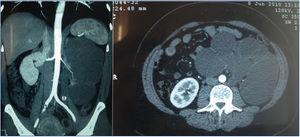

- Angio-TAC (tomografía axial computarizada): litiasis y ureterohidronefrosis izquierda máxima que provoca tracción de la arteria renal ipsilateral (figura 1).

En cuanto al diagnóstico por imagen, en la ecografía no se visualizó imagen clara de litiasis renal, debido muy posiblemente a la localización ureteral del cálculo, evidenciándose claramente en la TAC y en la pieza quirúrgica. La TAC tiene, de igual forma, mayor sensibilidad que la ecografía para detectar litiasis renal < 5 mm, así como otras anomalías renales10. No se realizó eco-Doppler por las características antropométricas de la paciente (obesidad), indicando directamente angio-TAC bajo protocolo de nefroprotección, dada la presunción de nulidad funcional unilateral.

La patofisiología por la que esta paciente desarrolló HTA a los 34 años de edad la entendemos como multifactorial: a) el estiramiento de la arteria renal por tracción del riñón hidronefrótico provoca estenosis de esta, y con ello activación del sistema renina angiotensina-aldosterona (RAAS), de forma similar a lo ocurrido en algunos casos de ptosis renal11. Aunque no disponemos de imágenes previas para establecer un diagnóstico diferencial con arteria renal hipoplásica, la paciente refiere control ecográfico de sus gestaciones sin alteraciones; b) la litiasis renal condiciona un estado de uropatía obstructiva y con ello la formación de quistes uriníferos que comprimen el parénquima renal, activando también el RAAS12; c) la inflamación intersticial como respuesta inmune a la infección urinaria reduce el área de los capilares peritubulares, dificultando el mecanismo de natriuresis por presión13. Se entiende que la ARP de la paciente estaba en rango normal por su supresión en el riñón contralateral, además de que, en la mayoría de los individuos, esta cifra se encuentra normal una vez ya establecida la HTA14. La excreción elevada de sodio en orina nos indica ingesta elevada de este, y su excreción fraccional < 1 %, un aumento en su reabsorción tubular (la uropatía obstructiva que también puede reflejarse de esta forma es en riñón no funcionante con 0 % de participación en la gammagrafía), a pesar de presentar dosis bajas de diurético tiazídico.

Figura 1. Angio-TAC.